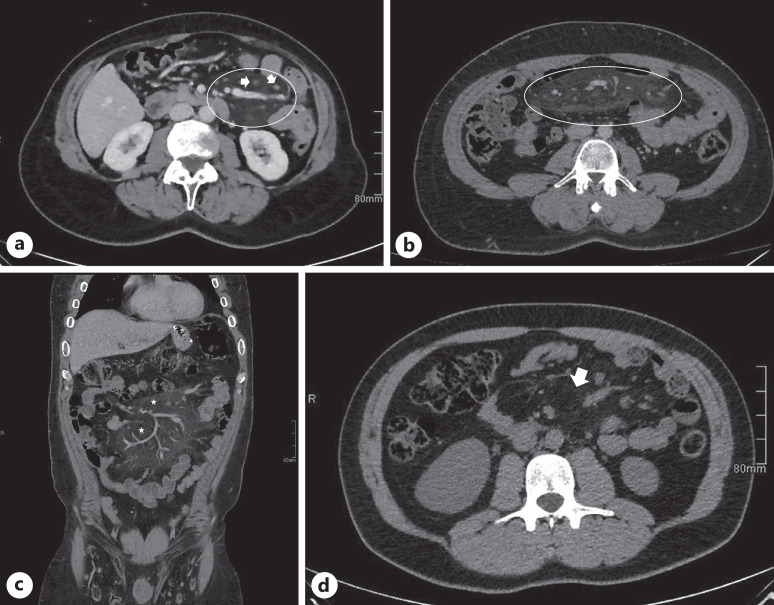

Background: Mesenteric panniculitis (MP) is an uncommon non-neoplastic idiopathic inflammation of adipose tissue, mainly affecting the mesentery of the small intestine, with its etiology remaining largely speculative. The difference in prevalence of MP among females and males varies across multiple studies. In most cases, MP is asymptomatic; however, patients can present with nonspecific abdominal symptoms or can mimic underlying gastrointestinal and abdominal diseases. The diagnosis is suggested by computed tomography and is usually confirmed by surgical biopsies if necessary. Treatment is generally supportive and based on a few selected drugs, namely, nonsteroidal anti-inflammatory drugs or corticosteroids. Surgery is reserved when the diagnosis is unclear, when malignancy is suspected or in the case of severe presentation such as mass effect, bowel obstruction, or ischemic changes.

Summary: MP is a rare inflammatory condition of the mesentery often asymptomatic but can cause nonspecific abdominal symptoms. Diagnosis relies on computed tomography imaging, with treatment mainly supportive, utilizing medications like nonsteroidal anti-inflammatory drugs or corticosteroids, while surgery is reserved for severe cases or diagnostic uncertainty.

Key messages: MP causes abdominal pain, and it is mainly diagnosed with CT scan.